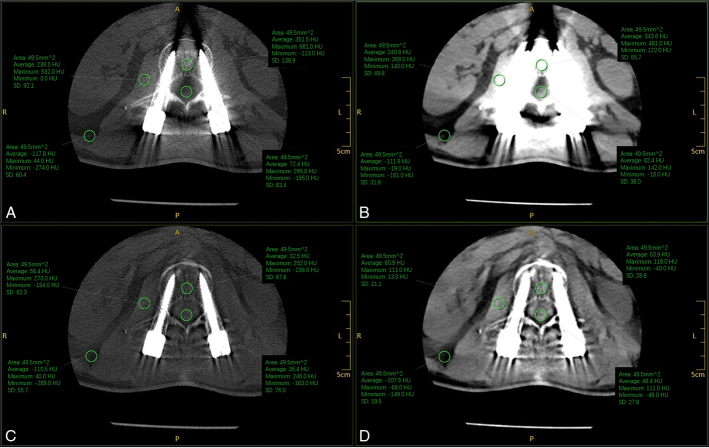

Materials and methods: A total of 57 patients who underwent lumbar spine CT examination after lumbar internal fixation from January to December 2023 in our hospital were retrospectively enrolled. The CT images were reconstructed using MAR + and non-MAR + techniques and were subdivided into MAR + and non-MAR + groups. The CT number (in Hounsfield units) and the SD noise values of the spinal canal, vertebral body, psoas major muscle, and adjacent fat were measured in the 2 groups of CT images, and the signal-to-noise ratio (SNR) and contrast-to-noise ratio (CNR) were calculated. The subjective score was evaluated by two diagnostic radiologists using a double-blind method for image quality evaluation of the MAR + group and the non-MAR + group, and the image quality was classified on a 5-point scale. The rank-sum test was utilized to compare the subjective and objective scores of the 2 groups.

Results: The SD values of the spinal canal ( Z =-4.12, P <0.01), vertebral body ( Z =-3.81, P <0.01), and psoas major muscle ( Z =-3.87, P <0.01) in the MAR + group were significantly lower than those in the non-MAR + group ( P <0.05). However, the SD values of the adjacent fat ( Z =-2.03, P =0.42) in the MAR + group, although smaller than those in the non-MAR + group, were not statistically significant. The CNR values of vertebral canal ( Z =-2.67, P =0.008) and fat ( Z =-2.60, P =0.009) were higher in the MAR + group than in the non-MAR + group, whereas the CNR values of the vertebral body ( Z =-6.74, P <0.01) in the MAR + group were smaller than those in the non-MAR + group, and the difference of all of them was statistically significant ( P <0.05). Furthermore, for both CT and SNR values, the MAR group's values were all less than those of the non-MAR group and were statistically significant ( P <0.05). The subjective scores of the measurement points were all higher in the MAR + group than in the non-MAR + group.

Conclusions: The MAR + technique has a noise reduction effect on different tissues and artifacts are significantly reduced. Although the artifacts caused by metal screws were not completely eliminated, the MAR + technique was able to reduce the interference of artifacts in the diagnosis of CT images, thus improving their diagnostic quality.